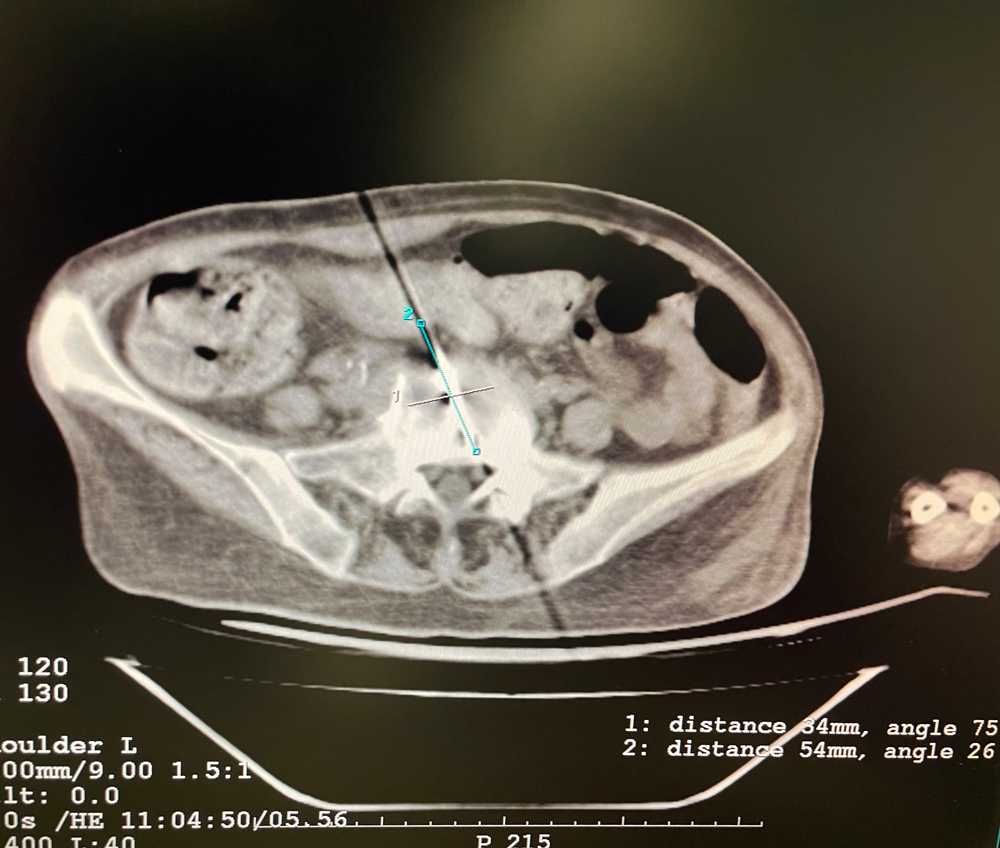

患者二

女,42歲,復發性脂肪瘤,病灶位于右側膝關節,直徑大小13cm。采用雙針方案,共進行6個凍融循環,最大冰球直徑達8.2cm,術中多方位治療全面覆蓋病灶范圍。患者術后狀況良好。